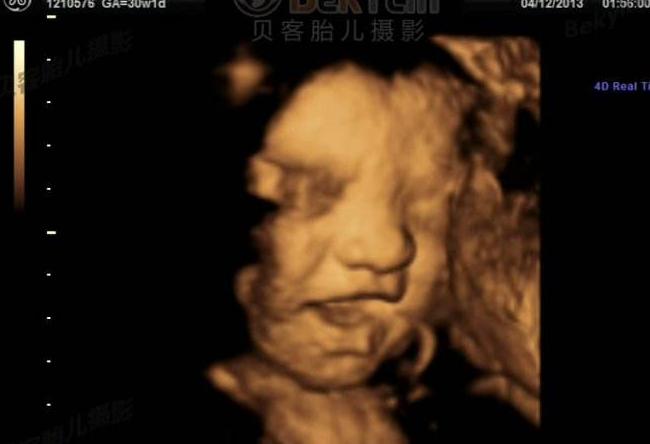

答:高清四维彩超是一种尤为先进的彩色超声设备,不仅能显示胎儿的实时动态活动图像,关键是能为胎儿健康排畸保驾护航,能获得清晰的胎儿面部立体图像,和多方位、多角度地观察胎儿各器官发育情况以外,更重要的是,还可以排查胎儿是否患有唇裂、脊柱裂、骨骼发育不良等先天畸形等,以便尽早进行治疗,让准妈妈生个聪明健康的孩子。

高清四维彩超采用先进超声影像技巧,在立体成像方面效果更佳,层次感、分辨率和准确度最高,能模拟子宫内环境和色彩,清晰观察到胎儿每个部位的发育情形,具有高度灵敏和精准的排畸诊断效果。相比传统彩超而言,有着更为清晰的画面,可以让医生更为有效的观察胎儿在孕妇腹中的情况,更加有效的判断出胎儿的身体有无异常、发育是否完好。

高清四维彩超,能够全方位、多角度观察宫内胎儿的生长发育情况,可以清晰地反应出胎儿畸形的种类和部位,提高了诊断和排畸的准确率;与此同时,还可以检测出准妈妈身体内部的健康情况,为母婴健康保驾护航。自投入临床使用后,受到众多孕妈妈的喜爱。它的检测排畸功能是目前所有彩超中全面,准确的,检测全面率相比于同类彩超来说达到了90%以上。